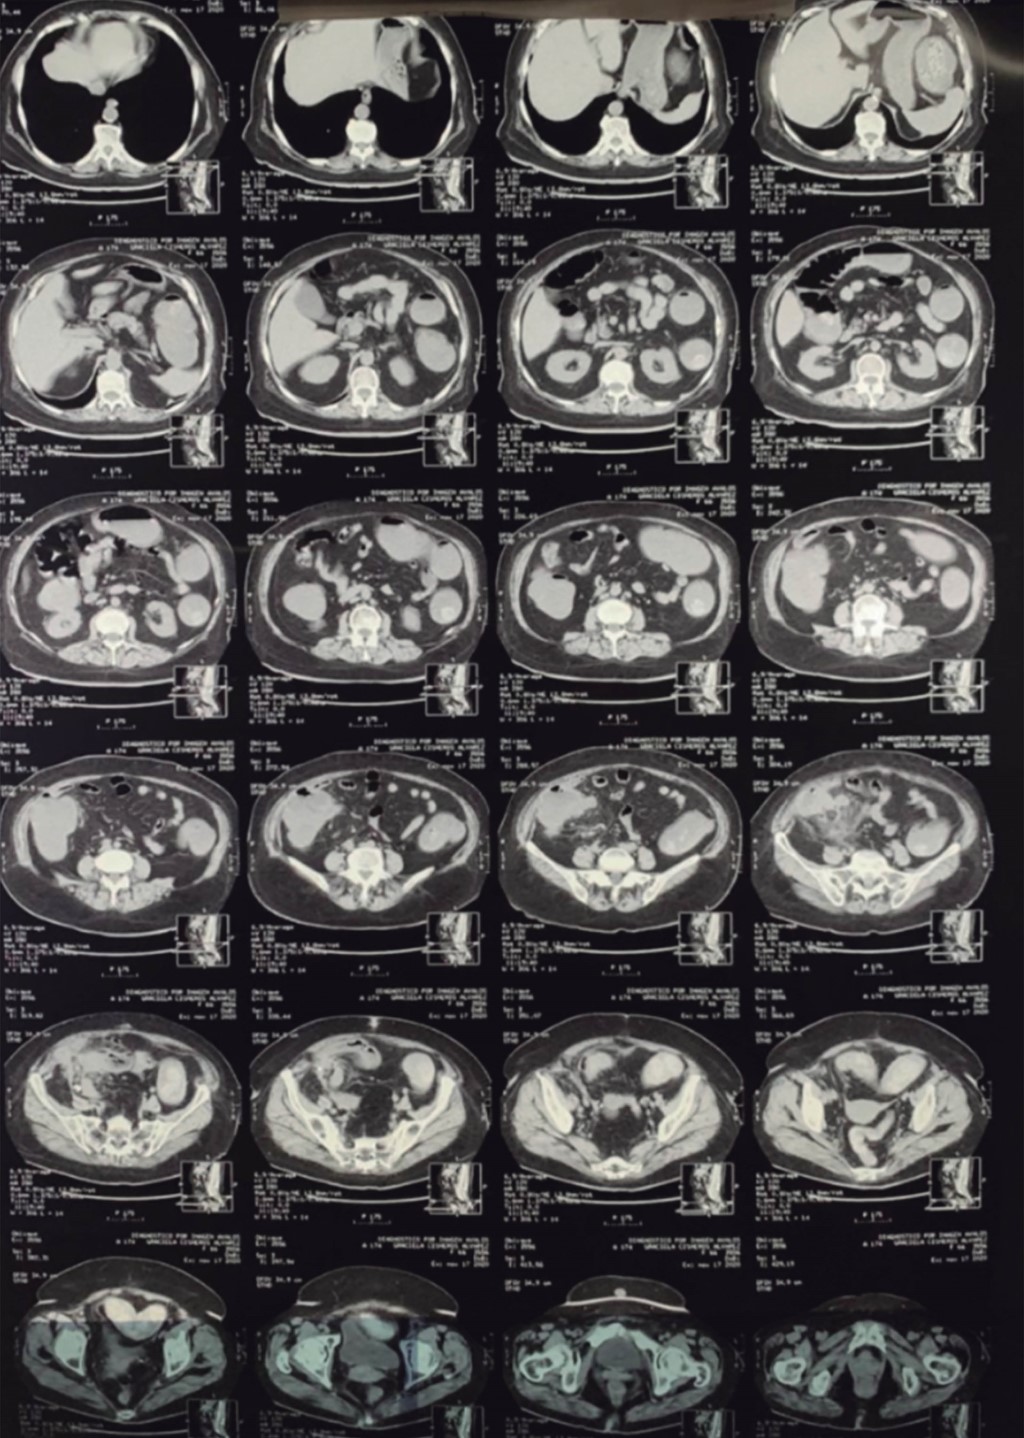

A 66-year-old female patient with a history of type 2 diabetes of 40 years of evolution treated with insulin, and high blood pressure of 25 years of evolution treated with ACE inhibitors is presented; she had a history of an umbilical hernia repair 14 years ago, a cesarean section 34 years ago, and a clavicle fracture two years ago. She was admitted to the emergency department for presenting abdominal pain located in the right iliac fossa; the abdominal pain was chronic, with more than six months of evolution; it had been present but had subsided. The previous week, she began with abdominal pain located in the right iliac fossa, which subsided with medication. She also had symptoms of intestinal occlusion without being able to pass gases, and she did not present vomiting. Examination revealed tachycardia, peritoneal irritation in the right iliac fossa, a palpable measuring 7 × 10 cm in the right iliac fossa and significantly decreased peristalsis. An abdominal tomography was performed (Figures 1 and 2), where a tumor was observed with probable perforation, which was mentioned as probable complicated appendicitis vs. tumor. It was decided to perform an exploratory laparotomy, finding a non-purulent inflammatory reaction liquid of approximately 100 ml; a tumor was observed emerging from on the cecum and invading the sigmoid colon, so it was decided to perform a right hemicolectomy with ileostomy and closure of the distal end, and a 7 cm resection of the sigmoid colon. An end-to-end sigmoid anastomosis with manual technique with non-absorbable suture was performed. Closed drains were placed towards the right slider, and a closed drainage was placed on the pelvic space. Pathology pieces were taken and sent to pathology analysis. The surgical procedure was completed; she went to the recovery room and then to her hospital room. She was instructed to fast for 24 hours, and then an enteral diet was started. Seven days after surgery, the drains were removed without complications. She was referred to the Infectious Diseases Department, which gave her a course of antibiotics based on tetracyclines for six weeks. The pathology report showed a hemicolectomy region (Figure 3) without alterations of the lymphoid tissue in Peyer's patches, and fibrin pseudo membranes with neutrophils that were deposited in the serosa. The ileocecal valve and cecal ascending mucosa showed mixed inflammatory reaction with numerous pyocytes extending to the adipose tissue of the mesoappendix that harbors bacterial colonies of Actinomyces spp. that form branching filaments and radial crowns forming sulfur granules (Figure 4). The cecal appendix demonstrated acute fibrinopurulent peri appendicitis, and the sigmoid tissue had pronounced edema in its walls. The diagnosis was a perforated cecal invasive Actinomyces with secondary acute fibrinopurulent peritonitis. The patient was discharged and seen in the general surgery outpatient department with favorable evolution. The infectious disease service recommended waiting at least six months free of inflammatory activity and medical treatment with antibiotics before intestinal reconnection was attempted.

Figure 1

Figure 2